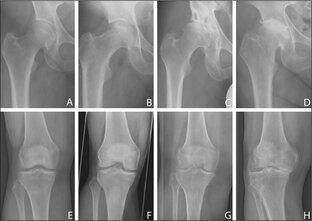

Характерные для остеоартита проявления: 🟡 боль механического характера, усиливается по ходу увеличения нагрузки, склонна к прогрессированию; 🟡 стартовая боль, возникает в начале движения; 🟡 скованность в суставах по утрам до 30 минут; 🟡 хруст в суставах; 🟡 ограничение движений в суставах; 🟡 деформация суставов. Отличительных лабораторных признаков нет. Инструментальные исследования: 🟢 Рентгенография - самый простой и достоверный метод обнаружения сужения суставной щели и костных выростов (остеофитов)...